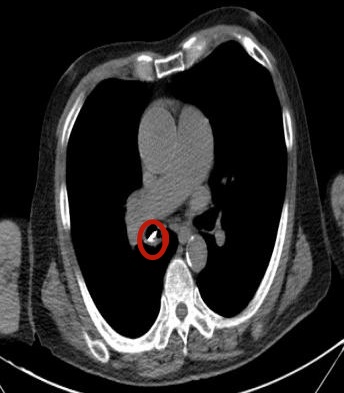

急诊医生给他做了胸部CT平扫,气管里面果然有个高密度影,考虑就是误吸的排骨。

红圈处为老人误吸的排骨碎片